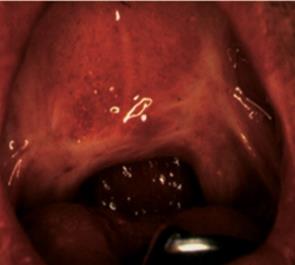

7.3.ábra. A beteg erősen hegesedett elülső garatíve